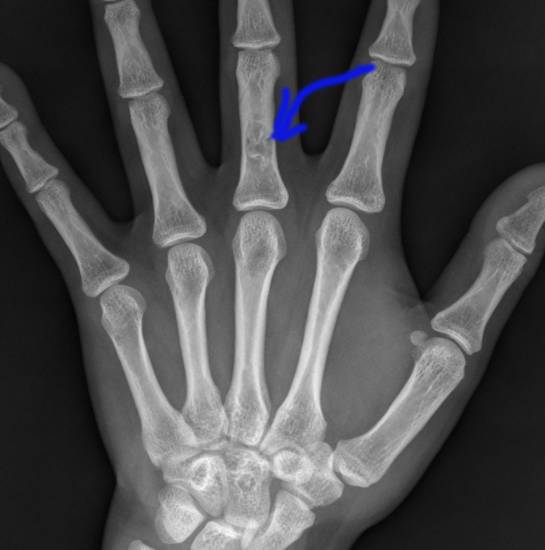

Энхондромы (центральные) – самый распространённый вид хрящевых опухолей. Локализуются в местах, где в норме нет хрящевых тканей, и располагаются внутри кости. Предполагается, что новообразование формируется из остатков хрящевых пластинок, которые со временем постепенно увеличиваются. В процессе развития энхондромы деформируют кость, распирая её изнутри. Обычно образуются в костях кисти (на фалангах пальцев) и стопы. Реже встречаются в подкожной клетчатке и межмышечной ткани, в яичках, в молочной и подчелюстной железе, в околоушной и слёзной железе, в головном мозге, лёгких и яичниках. Чаще всего энхондромы бывают одиночными, но встречаются и множественные – энхондроматоз, который называется ещё болезнью Оллье.

Энхондрому в костях скелета, кроме области основания черепа, можно выявить обычным рентгенологическим исследованием. Например, при локализации подобной опухоли на рёберной дуге слева, сделав рентген, можно увидеть очаг дисплазии и кистозную опухоль. Экхондрома не рентгеноконтрастна, её невозможно разглядеть на рентгеновских снимках на фоне мягких тканей.

Кроме рентгена обычно назначаются следующие исследования: